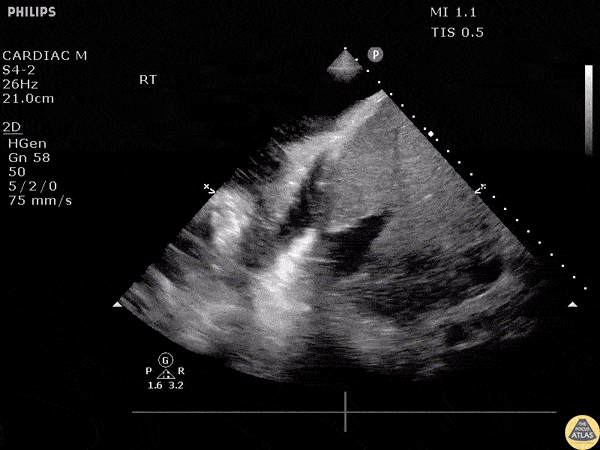

Large echogenic right parapneumonic effusion in patient with bacterial pneumonia/sepsis. Phased array probe used. Image courtesy of Robert Jones DO, FACEP @RJonesSonoEM Director, Emergency Ultrasound; MetroHealth Medical Center; Professor, Case Western Reserve Medical School, Cleveland, OH View his original post here